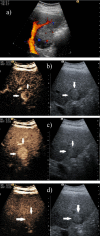

Hepatocellular carcinoma is a major health issue, ranked the fifth most common tumor and currently being responsible for a third of the cancer-related deaths globally, with an ever-increasing number of fatalities. Current advances in contrast-enhanced imaging techniques such as contrast-enhanced ultrasonography, multi-detector computed tomography and diffusion-weighted magnetic resonance imaging are improving the rate of hepatocellular carcinoma diagnosis. Contrast-enhanced ultrasonography has widely become the first choice in liver tumor assessment, as it is faster, simpler and safer than other forms of diagnostic imaging. On the other hand, cross sectional computed tomography is frequently employed when a hepatic formation is suspected of malignancy and allows a more accurate characterization of lesions through multiphasic multi-detector computed tomography technology. Diffusion weighted magnetic resonance imaging represents another addition to the wide range of diagnostic and prognostic techniques available for patients with hepatocellular carcinoma and is currently regarded as one of the best tools for the characterization of these lesions. Furthermore, groundbreaking biomarkers for hepatocellular carcinoma are being discovered, although alpha-fetoprotein remains one of the most frequently used serum test in the early stages. Nonetheless, further advances are required for the detection of small liver carcinomas.